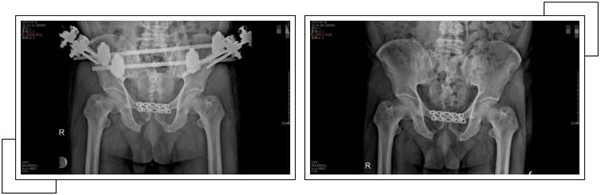

二周后,趙大叔病情穩(wěn)定,身體各方面條件符合手術(shù)指征后,骨科中心副主任羅軍帶領(lǐng)手術(shù)團(tuán)隊(duì)為其進(jìn)行了骨盆骨折、恥骨聯(lián)合分離、雙側(cè)髂骨骨折、右側(cè)恥骨上下支骨折切開復(fù)位內(nèi)外固定術(shù),手術(shù)一個(gè)半小時(shí)順利完成。

經(jīng)過關(guān)節(jié)科全體醫(yī)護(hù)人員的精心治療和護(hù)理,術(shù)后一個(gè)月,趙大叔康復(fù)出院。出院當(dāng)天,趙大叔感謝的話說了又說,并在來復(fù)查時(shí),特地制作了一面錦旗以表示謝意。